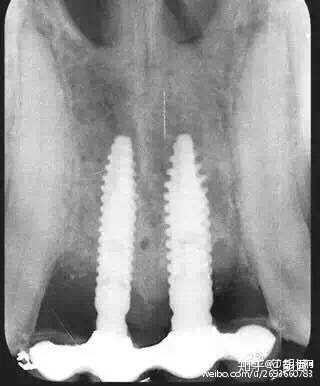

狗狗牙齿脱落后给狗狗做的种植牙